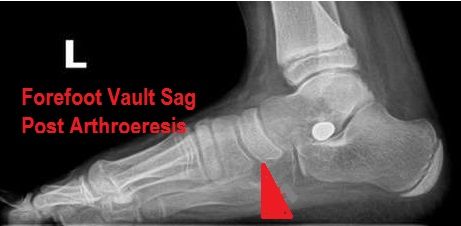

This case reinforces my position that many cases of arthroeresis need adjacent Foot Centering orthotics that support the vaulted position that the implant is placing the foot in, as well as to compensate for pre-existing forefoot pathology that the stent cannot completely offset. The x-rays seem to reflect a well-placed, well-sized subtalar stent, but reveal the fact that there is continued collapse of the forefoot vault (see x-ray below).

Forefoot Vault Sag Post-Arthroeresis |

I assume that, in this case, it is the obesity of the patient, age, activity level, SERM-PERM Interval, foot type, and other factors also come into play when deciding to couple a Foot Centering with an STJ implant. Before giving up, you should cast and dispense a vaulted orthotic in lieu of the subtalar joint neutral devices you probably dispensed when you mentioned that you have failed with orthotic intervention in this case.